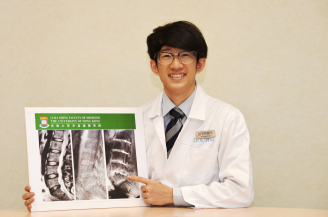

是次研究的首席作者、香港大學李嘉誠醫學院醫學研究碩士學生彭亨利醫生亦指出:「於芸芸眾多的磁力共振(MRI)當中,港大的研究人員發現UTE MRI是唯一能精準評估臨床指標及診斷腰背痛的嶄新影像技術。而同時,UTE MRI 亦能找出傳統 MRI未能發現的全新病徵。因此,我們相信這項新發現對揭示腰椎退化的成因及制定針對性的腰背痛治療有重大幫助。」

這次研究共有108名華南地區人士(平均年齡52歲,男女各半)參與。傳統的T2W MRI用作評估椎間盤退化和其他影像病徵,T1-rho MRI用作量度構成椎間盤的主要成份 “蛋白聚醣”水平。UDS 病徵被定義為在UTE MRI上檢測到的超高或超低光束帶。參與者的基本資料、病歷、腰背痛情況及活動能力指標(ODI Oswestry Disability Index)亦於研究時採納為臨床指標之一。

研究結果發現39.8%的參與者有UDS病徵,而其中61.4%的UDS是發生於下腰部位置。有UDS病徵比沒有UDS病徵的參與者有更多機會患有椎間盤退化、椎間盤突出、脊椎移位及椎體變異(Modic Change)。有UDS病徵的椎間盤的蛋白聚醣含量比沒有UDS的椎間盤低。而逾六成UDS病徵是無法在傳統的T2W MRI上檢測到。有UDS病徵的參與者比沒有的參與者有更嚴重的腰背痛,而同時其活動能力亦較差,而傳統的T2W MRI並無法找出此關連。研究更指出約四成患者於多節腰椎皆出現UDS病徵,其患上嚴重腰背痛的機率比單節腰椎出現UDS的患者更高。